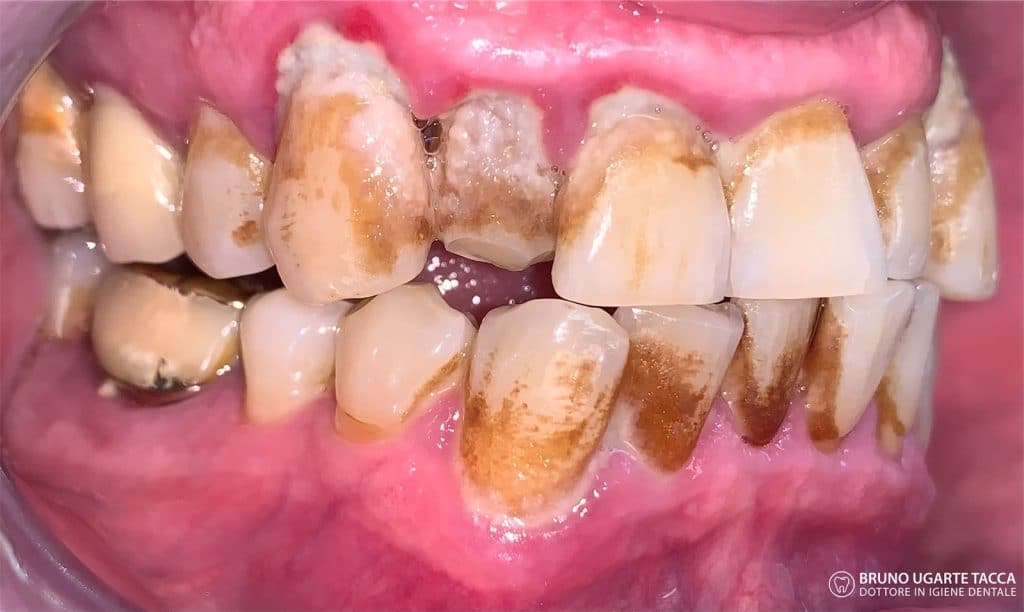

Performing the complete instrumentation

supragingival and subgingival with ultrasonic and / or manual instruments in one

single session or in two sessions at most performed over 2 days